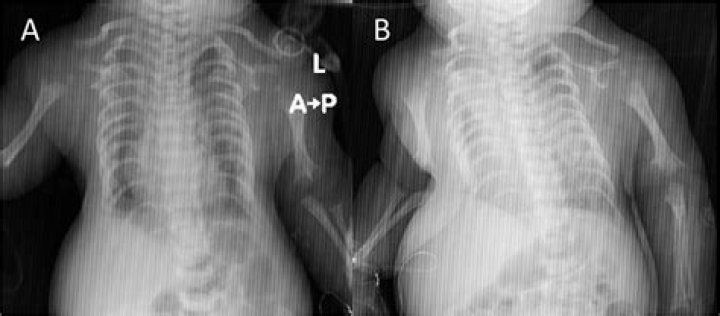

Treating Jeune syndrome - Prof. Drebov, Pirogov Hospital, Sofia, Bulgaria

Asphyxiating thoracic dystrophy (ATD) is a very rare form of skeletal dysplasia that primarily affects development of the bone structure of the chest (thorax) resulting in a very narrow and bell-shaped chest.

Also called asphyxiating thoracic dystrophy. Children born with Jeune syndrome have a small chest and ribcage. The child may have life-threatening breathing problems because there isn't enough room in the chest for the lungs to develop properly or to expand fully during breathing.

Description. Collapse Section. Asphyxiating thoracic dystrophy, also known as Jeune syndrome, is an inherited disorder of bone growth characterized by a narrow chest, short ribs, shortened bones in the arms and legs, short stature, and extra fingers and toes (polydactyly).